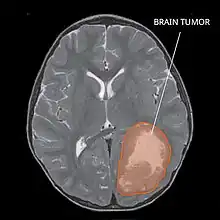

| Primitive neuroectodermal tumor of the central nervous system in a 5-year-old |

A central nervous system primitive neuroectodermal tumor, often abbreviated as PNET, supratentorial PNET, or CNS-PNET,[1] is one of the 3 types of embryonal central nervous system tumors (medulloblastoma, atypical teratoid rhabdoid tumor, and PNET).[2] It is considered an embryonal tumor because it arises from cells partially differentiated or still undifferentiated from birth.[1] Those cells are usually neuroepithelial cells,[1][2][3] stem cells destined to turn into glia or neurons.[4] It can occur anywhere within the spinal cord and cerebrum and can have multiple sites of origins, with a high probability of metastasis through cerebrospinal fluid (CSF).[1][2]